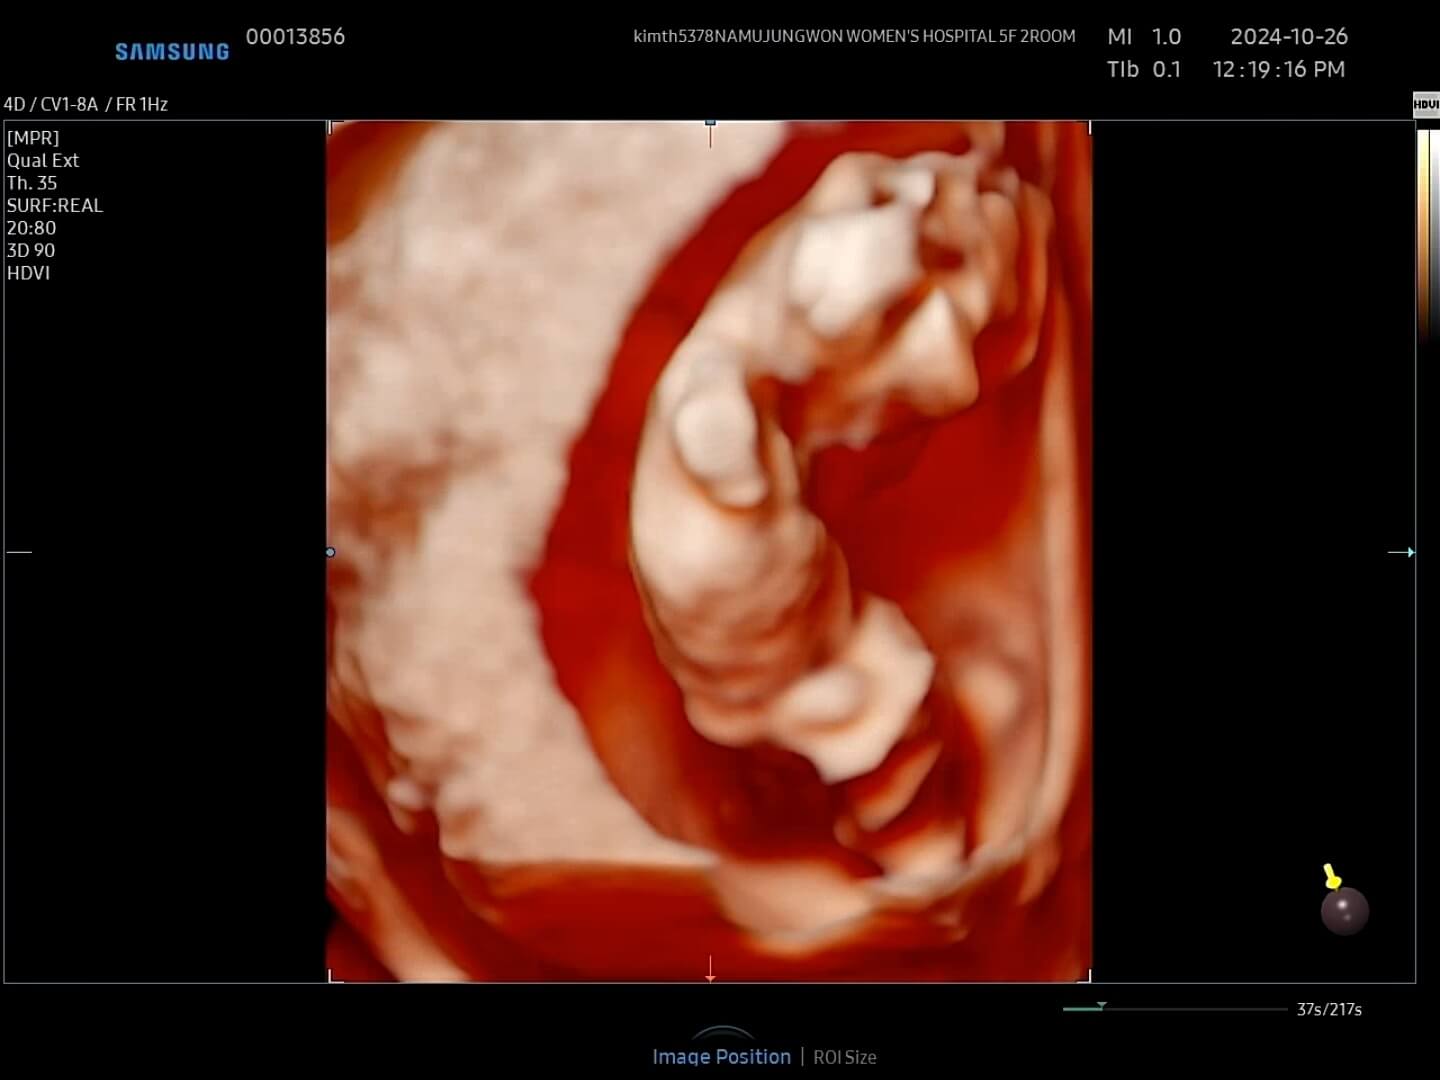

4. 12주 입체초음파

드디어 12주가 되어 꾸미의 첫 입체초음파를 보는 날이 되었어요! 두근두근, 꾸미는 얼마나 커있을까요?

12주-입체초음파 12주에는 첫 입체초음파를 보게 되면서 팔, 다리가 잘 형성되었는지 정도를 보는 것 같아요. 12주부터 '태아'라고 부르기도 한답니다. 우리 꾸미는 처음에는 등을 돌리고 있다가 서서히 얼굴을 보여줬습니다. 벌써부터 귀여워요! 아들인지 딸인지 너무 궁금했는데요, 성별은 입체 초음파가 아닌 일반 초음파로 봐야한다고 하셨어요.